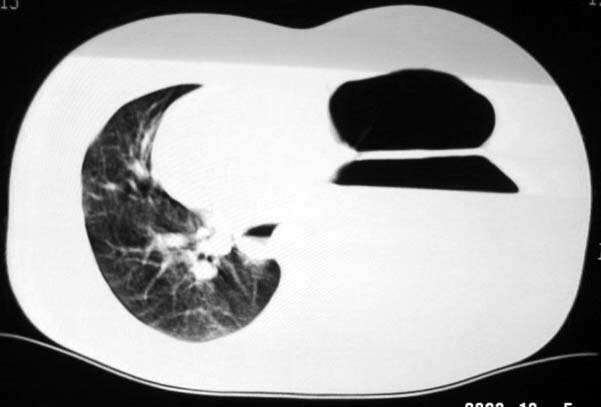

标题: CT5517:女性、24岁,反复胸痛、气促不能平卧半月。 [打印本页]

标题: CT5517:女性、24岁,反复胸痛、气促不能平卧半月。

左肺可见二个含气或液气的囊状影,左肺段支气管、左肺动脉显示不清,纵隔右移,考虑:左肺支气管肺囊肿,左肺发育不良,纵隔疝。

左侧气液腔与胃腔影相连,考虑膈疝。钡餐检查有助于诊断。

我看这是膈疝,在纵隔窗第六\\七幅图像上可见胃粘膜影,再者可见两个腔影,这在液气胸是不会有的.

液气胸 怎么会有2 个大腔?

左肺发育不良、支气管囊肿 应该纵隔左移的多吧

还是个膈疝